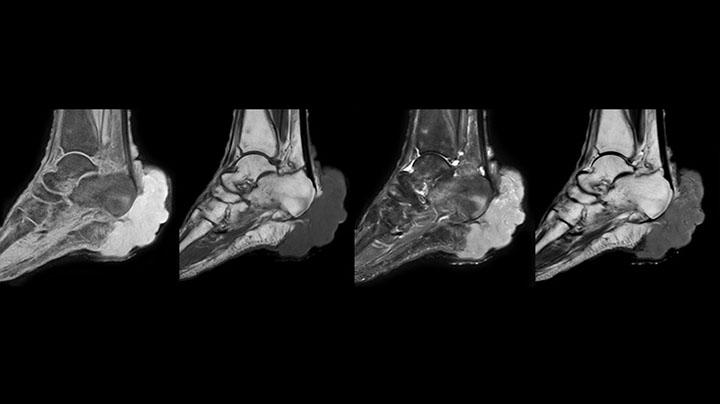

MR-Untersuchung mit Prodiva 1.5T, 72-jährige Patientin mit malignem Melanom am Knöchel. mDIXON TSE bietet eine hervorragende Fettsuppression ohne Verzerrung, wie sie ansonsten bei diesen Extremitäten häufig auftritt.